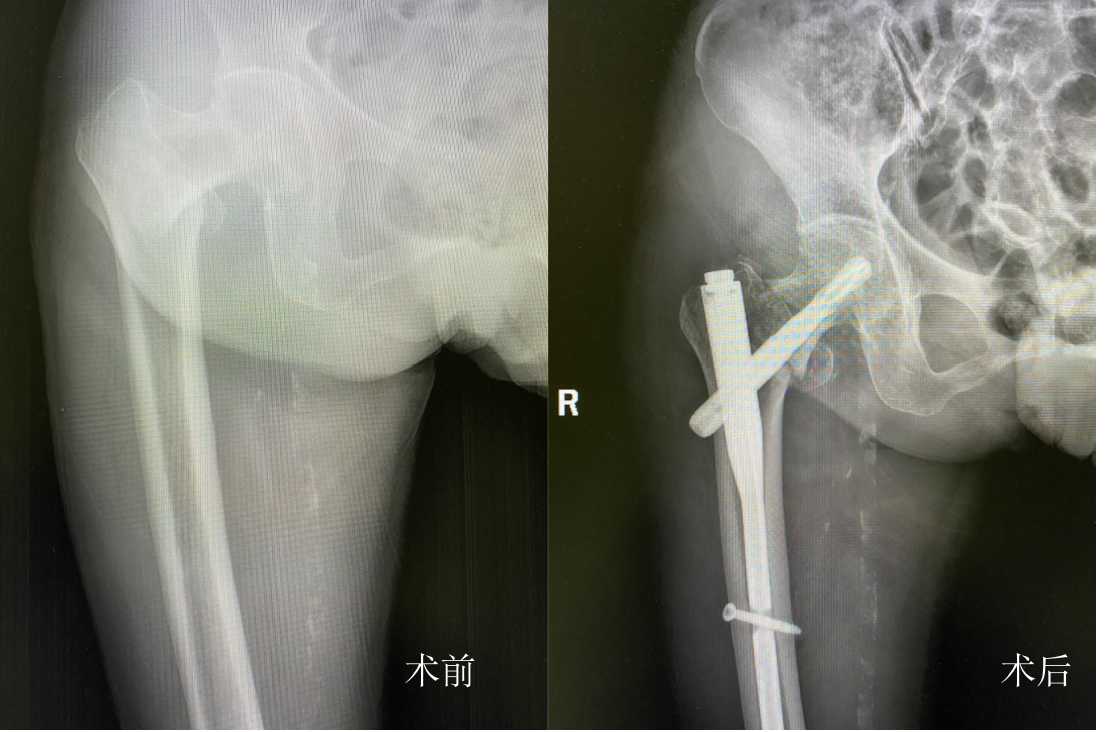

11月27日,今年96岁的卢奶奶在家不慎摔倒致右髋部疼痛,紧急送往中南大学湘雅三医院急诊就诊,行X线检查诊断为“右股骨转子间骨折”。以创伤骨科主任罗令为中心的老年髋部骨折多学科合作(Multiple Disciplinary Team,MDT)团队开通绿色通道,当日即转入骨科26病区,在经过骨科、麻醉科、血管外科、心血管内科、护理团队精准术前评估后,24小时内完成骨折内固定手术。术后恢复情况良好,第二天即下地行走,患者本人及家属对手术效果非常满意,并于12月3日已顺利出院。

完善术前检查后,罗令团队为患者实施了“右股骨转子间骨折开放复位髓内钉内固定术”,结合团队独创的“无牵引床”复位技术,并全程在G臂透视下进行定位,大大缩短手术时间,手术用时不到15分钟,手术切口不足5公分,出血量不足50ml。同时,为最大程度缩短手术时间,医生需身穿铅衣,全程在射线下进行手术。当手术完成的那一刻,罗令教授脱下30斤重的铅衣,他的整个后背已被汗水浸透。术后第二天卢奶奶便恢复了站立并缓慢行走,良好的手术效果及康复获得了患者及家属的连连称赞。